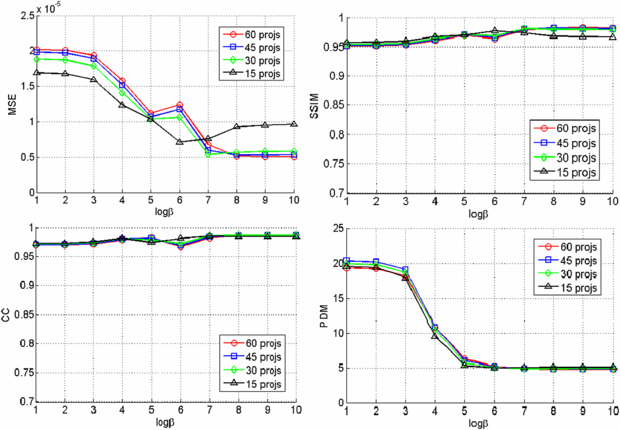

Since we used six beads for registering the CBCT prior volume to the post-injection x-ray projections and there is no soft tissue in the phantom, the registration was very accurate and the difference images clearly show the region of change while other structures are eliminated as shown in figure 3. The VOCs reconstructed from 15, 30, 45, 60 difference images by the PL reconstruction method with different β values (101–1010) were compared to the CBCT ground truth, and figure 4 shows the similarity measure plots as a function of β. It is observed that the reconstruction is noisier at lower β where the estimate is closer to ML estimate, but becomes smoother at higher β where the reconstruction is more regularized by the penalty. Since the shape and structure of the bone cement was not so complicated and the registration was accurate, the overall reconstruction quality was not degraded even when we reduced the number of images and the similarity plots show similar reconstruction performance regardless of the number of images. It is also observed from these plots that the overall reconstruction quality is lower at lower β because it is noisier, but is similarly good when β becomes large. Figure 5 shows an example of slice images of the VOC reconstruction computed from 15 projections after 100 iterations with β = 107 (chosen from figure 4) and its fusion with the prior volume. The reconstructed VOC with prior volume showed significantly reduced artefact compared to the FBP reconstruction (Feldkamp et al 1984) computed from the same 15 post-injection x-ray images.

Standard imageFigure 4. Similarity measures for different number of projections and β values.